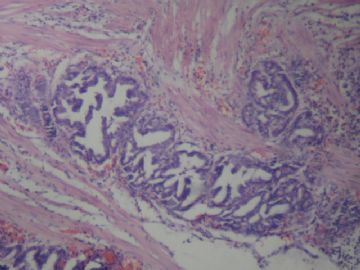

• 胆囊图2

图2

慢性胆囊炎 腺体中度不典型增生

腺体重度异型增生(注意有无明确浸润)

在粘膜层,1、2图在粘膜浅肌层。未见明显浸润。

无明显浸润,诊断癌证据不足。

考虑慢性胆囊炎,局部腺体中重度不典型增生

诊断癌证据不足。慢性胆囊炎 腺体中度不典型增生

局部见腺体中度不典型增生。标记P53和增殖活性(Ki-67) 。

图1和2够不上浸润,因为这样的腺体似是因炎症而陷入的,类似于腺肌症。

不够癌,不典型增生-中度